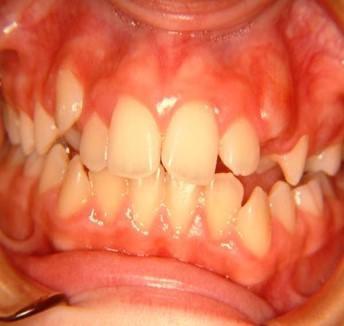

Γ3γ. έκτοπη ανατολή μονίμων δοντιών Συμβαίνει όταν το διάδοχο μόνιμο δόντι ανατέλλει σε άλλη θέση από τον πρόγονό του.

Εδώ παρατηρούμε τον κυνόδοντα να ανατέλλει ανάμεσα στον κεντρικό και πλάγιο τομέα. Η έγκαιρη ορθοδοντική παρέμβαση στην κατάλληλη ηλικία προλαμβάνει μελλοντικές συγκλεισιακές ανωμαλίες.